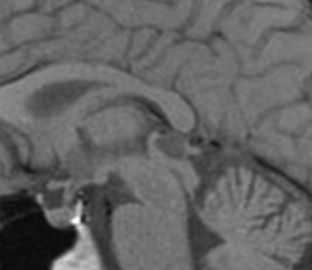

МРТ головного мозга. Т1-взвешенная сагиттальная МРТ. Арахноидальная киста в области большого затылочного отверстия.

МРТ головного мозга. Т1-взвешенная сагиттальная МРТ. Пинеальная киста.

МРТ головного мозга. Сагиттальная Т1-взвешенная МРТ. Пинеальная киста.